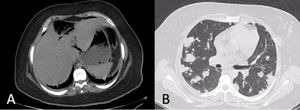

Presentamos el caso de una paciente de sexo femenino de 23 años con antecedente de diabetes mellitus tipo 2 que ingresa a urgencias por presentar dolor abdominal difuso, náuseas, vómito y fiebre de 3 días de evolución. El dolor se intensifica, irradiándose a epigastrio e hipocondrio derecho. Presentaba signos vitales de 131 latidos por minuto, 24 respiraciones por minuto, tensión arterial de 110/60mmHg y 38.6 ̊C de temperatura. A la exploración física presentaba ruidos crepitantes bibasales, abdomen con dolor difuso a la palpación abdominal con datos de irritación peritoneal. Los análisis de laboratorio reportaron una leucocitosis de 19,280cel/mm3 con neutrófilos de 79.8%. La glucosa al ingreso fue de 489mg/dl. El resto de los análisis de laboratorio eran normales. Se solicitó una radiografía de tórax, la cual reportó múltiples infiltrados bilaterales (fig. 1). Se realizó una tomografía computarizada simple de tórax y abdomen, en donde se reportó un grande absceso hepático roto de 6×7.1×3cm, formador de burbujas de gas en el lóbulo hepático derecho, sin presentar rotura diafragmática o datos de continuidad a tórax, además de neumoperitoneo con líquido libre en ambas correderas parietocólicas (fig. 2a). En el tórax se reportaron múltiples nódulos pulmonares cavitados compatibles con embolismos sépticos (fig. 2b). La paciente no había sido atendida previamente, por lo que se comenzó con administración de antibióticos de amplio espectro; sin embargo, el cuadro clínico empeoró de forma rápida, instaurándose un choque séptico que requirió vasopresores. Se llevó a la paciente a quirófano donde se realizó laparotomía de urgencia, encontrándose aproximadamente 1l de material purulento en la cavidad abdominal del cual se tomaron cultivos. Se tomó biopsia hepática para descartar malignidad. Se drenó el absceso identificado en el segmento iv y la paciente pasó en estado crítico a terapia intensiva. La paciente falleció 10h posteriores a su procedimiento quirúrgico. El resultado del cultivo reportó K. pneumoniae y la biopsia hepática reportó material fibrinopurulento.

Una de las complicaciones poco estudiadas son el embolismo séptico pulmonar descrito por Chou et al.7 quienes reportaron una tasa del 4.5% y un total de 14 casos, de los cuales el 83% presentaron diabetes mellitus y donde los síntomas prevalentes fueron fiebre y disnea. Solo un paciente en su serie presentó dolor abdominal en la admisión. De igual manera, los mismos autores consideraron que cuando un paciente diabético se presenta con fiebre, disnea y una radiografía de tórax con anormalidades que revelen múltiples opacidades y patrones infiltrativos, se debe de solicitar un ultrasonido de abdomen para descartar absceso hepático.